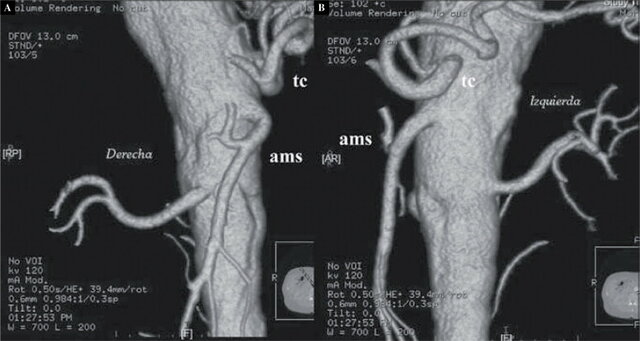

ASD-3D

La aparición de la angiografía con substracción digital y reconstrucción tridimensional (ASD-3D), en el año 2001, es el más importante desarrollo que ha ocurrido.